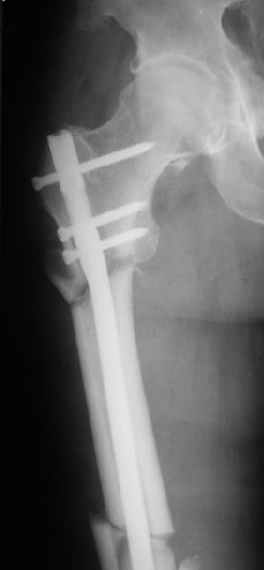

Это было года 2,5 назад, мы тогда еще уточняли возможности шинирования с угловой стабильностью гвоздем с поперечным расположением винтов при переломах проксимального отдела бедра. Пациенту не пришлось приобретать намного более дорогой рекон или проксимальный гвоздь. В приложении еще несколько примеров применения того гвоздя при высоких переломах бедра, в том числе с более латеральной точкой входа. Гвоздь изгибаем для этого.

Конечно, мы не синтезируем остеопорозые вертельные переломы согласно прилагаемому примеру, винты 6 мм вырежутся. Но у более молодых при хорошем качестве кости такие или подобные гвозди с поперечным расположением винтов вполне применимы для меж- и подвертельных переломов.